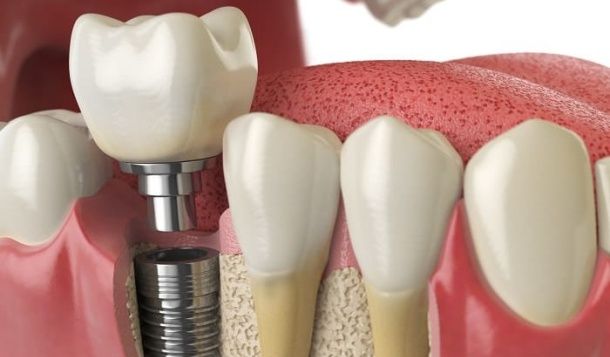

Los implantes dentales son raíces artificiales de titanio que se insertan en el hueso maxilar de los pacientes y sirven para soportar sus nuevos dientes fijos.

Los dientes implantados tienen un aspecto natural y son los que mejor recuperan las sensaciones de firmeza y confort de nuestros propios dientes. Se han convertido en una especialidad de resultados excelentes a la hora de sustituir piezas o completar tu dentadura de una manera estable, integrada, estética, y funcional. Nuestro equipo especializado te ofrece las últimas técnicas con las mínimas molestias y resultados más satisfactorios.

Al sustituir un diente con un implante, estamos restaurando no solamente la parte externa, sino también su raíz. Por eso, cuanto más hueso nos queda, mejor pronóstico tendrá el caso, y por eso no conviene dejar pasar el tiempo sin colocar los implantes después de las extracciones de dientes y muelas.